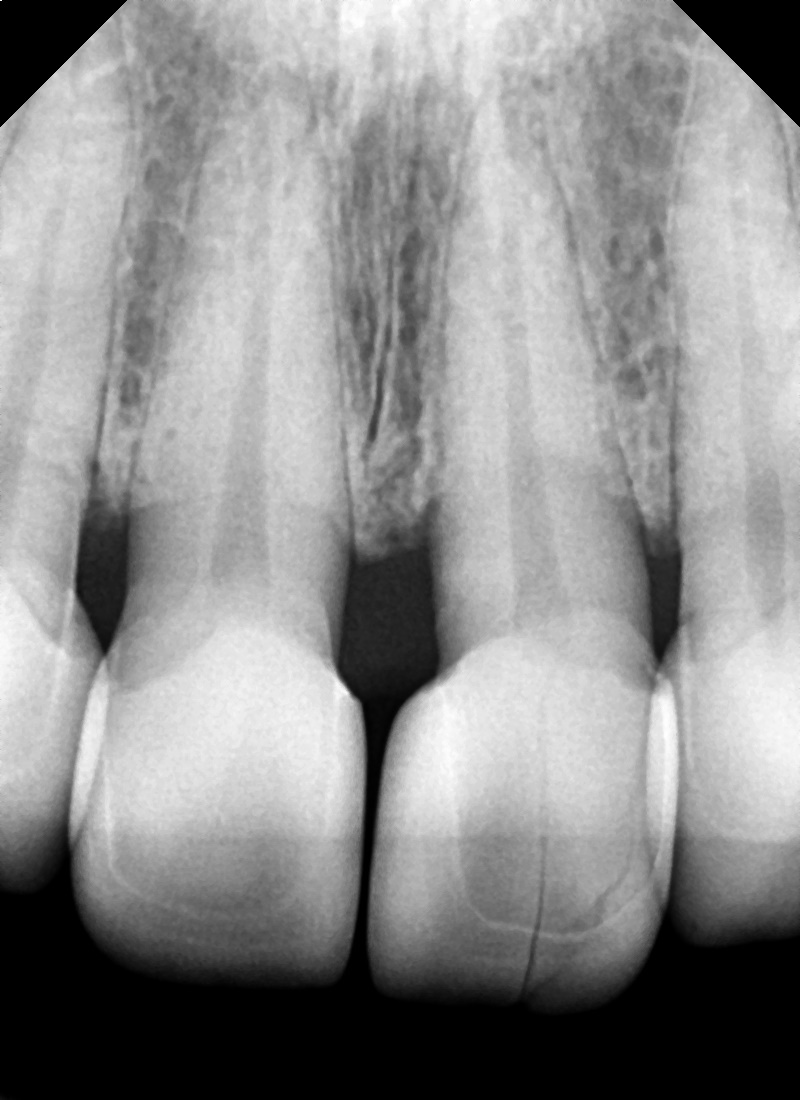

사실 처음 봤을 때 과거에 만드셨지만 너무 자연스럽게 잘하셔서 보철물이 아닌 자연치아인 줄 알았지만

사진에서와 같이 갈라지고 조각이 움직이고 있는 상태였습니다.

안쪽에서 보면 명확하게 보입니다.

앞니 4개를 하셨는데 그중에 2개가 금이 생겨있었습니다.

보철물이 파절이 되는 원인은

우리 치아의 교합은 시간이 지나면 계속 변하기 때문에

시간이 지남에 따라 앞니 사이의 교합 간섭이 일어나기도 하고

앞니를 안 쓸 순 없기 때문에

저작활동을 통해 보철물에 지속적인 하중에 가해지게 됩니다.